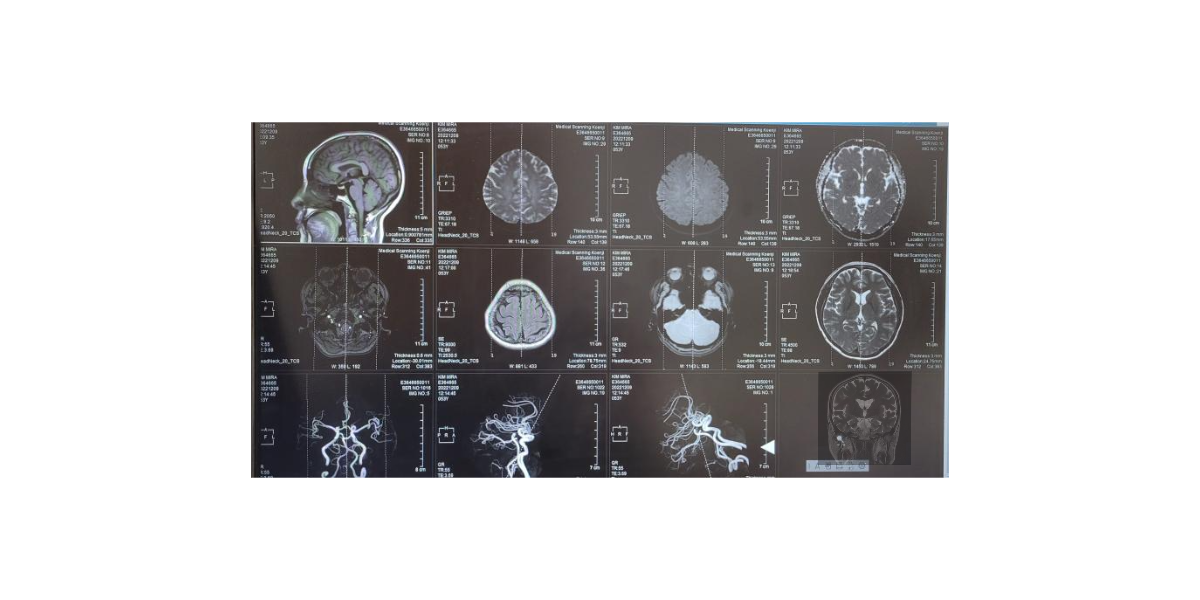

뇌졸중은 뇌혈관에 이상이 생기면서 발생하는 질환으로 크게 두 가지 유형으로 나뉜다. 하나는 뇌혈관이 막혀 발생하는 허혈성 뇌졸중이고, 다른 하나는 뇌혈관이 터져 생기는 출혈성 뇌졸중이다. 두 가지 모두 뇌로 가는 혈액 공급이 원활하지 않게 되면서 뇌세포가 손상되고, 이로 인해 다양한 신체적·인지적 장애가 나타난다. 가장 흔한 원인은 고혈압이다. 오랜 기간 혈압이 높게 유지되면 혈관 벽이 약해지고 경화가 진행되면서 결국 터지거나 막힐 수 있다. 특히 조절되지 않은 고혈압은 뇌출혈과 직접적인 관련이 있어 매우 위험하다. 그다음으로 흔한 원인은 당뇨병이다. 혈당 조절이 제대로 되지 않으면 혈관벽이 손상되고 염증이 생기면서 혈액 순환이 원활하지 않게 된다. 고지혈증 또한 주요한 원인이다. 혈중 콜레스테롤 수치가 높아지면 혈관 내벽에 지방이 쌓이게 되고, 이것이 플라크를 형성하면서 혈관을 좁히거나 막을 수 있다. 흡연 역시 뇌졸중 발생과 깊은 연관이 있다. 담배 속의 유해 물질은 혈관을 수축시키고 혈류 흐름을 방해하며, 혈압을 상승시킨다. 흡연은 특히 젊은 층의 뇌졸중 발생률을 높이는 요인으로 지목되기도 한다. 과도한 음주 또한 문제다. 술을 지나치게 자주 마시는 습관은 혈압을 급격하게 상승시키고 심장 기능에 악영향을 준다. 이러한 생활 습관 외에도 가족력이나 유전적인 요인도 뇌졸중 발병 가능성에 영향을 줄 수 있다. 이처럼 다양한 요인들이 복합적으로 작용해 뇌졸중이 발생하게 되므로, 단일 원인에만 집중해서는 안 된다. 특히 부모님 세대처럼 오랜 기간 누적된 건강 습관이 질병으로 이어질 수 있기 때문에, 평소 생활 습관을 점검하고 질환의 근본 원인을 이해하는 것이 무엇보다 중요하다.

뇌졸중은 예고 없이 갑작스럽게 찾아오는 경우가 많지만, 그전에 미세한 전조 증상들이 나타나는 경우도 많다. 이러한 초기증상들을 인지하고 빠르게 대응하는 것이 후유증을 줄이고 생명을 지키는 데 매우 중요하다. 가장 대표적인 증상은 한쪽 얼굴의 마비다. 웃을 때 입이 한쪽으로만 움직이거나, 얼굴 근육의 균형이 무너지는 경우 의심할 필요가 있다. 이런 증상은 뇌의 특정 부위에서 신경 전달이 원활하지 않아 생기는 결과로, 단순한 피로로 넘기기 쉽지만 매우 위험한 신호일 수 있다. 팔이나 다리에 갑작스러운 힘 빠짐 현상이 나타나는 경우도 흔하다. 물건을 들다가 떨어뜨리거나, 걷는 도중 다리에 힘이 풀리는 등 일상적인 동작 중 이상을 느낄 수 있다. 말이 어눌해지고 발음이 명확하지 않게 되는 것도 주요한 증상 중 하나다. 평소와 다르게 말이 느려지거나 단어가 잘 떠오르지 않고 말이 엉키는 경우는 뇌기능 저하의 초기 신호일 수 있다. 또한 갑작스러운 시야 장애도 주의해야 한다. 한쪽 눈이 잘 보이지 않거나 이중으로 보이는 현상은 뇌의 시각 중추에 문제가 생겼음을 의미할 수 있다. 심한 어지러움과 균형감각 상실도 초기 증상 중 하나로, 특히 넘어지거나 방향 감각을 잃는 경우 즉시 병원을 찾아야 한다. 가슴 통증이나 호흡 곤란과 함께 이런 증상이 동반된다면 더욱 심각한 상황일 수 있다. 중요한 것은 이러한 증상이 일시적으로 나타났다가 사라져도 절대 안심해서는 안 된다는 점이다. 뇌졸중은 경고 없이 재발하거나, 본격적인 발작으로 이어질 수 있기 때문에 가벼운 증상이라도 놓치지 말고 즉시 의료진의 도움을 받는 것이 중요하다.